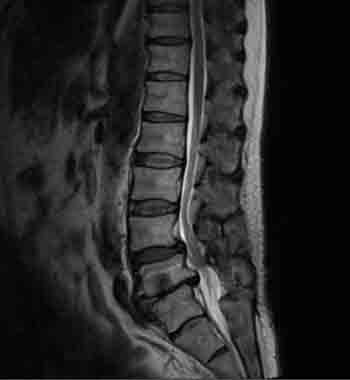

腰部脊柱管狭窄症の症例

脊柱管狭窄症の手術後も改善しなかった歩行困難が、AKA-博田法で改善した例

令和5年春頃、腰下肢痛と痺れにより、わずか数十メートル歩くだけでしゃがみ込まなければならない状態(間欠性跛行)になり、他院を受診。「腰部脊柱管狭窄症」と診断され、狭窄部を広げる手術を受けました。 しかし、術後も症状は全く改善せず、医師からは「再手術」を提案されました。再手術に強い不安を感じ、他の解決策を求めて同年に当院を受診されました。

当院で詳しく診察したところ、痛みの真の原因は脊柱管狭窄症ではなく、「仙腸関節」の動きの悪さ(機能障害)にあると判断しました。

今回のケースでは、画像診断上の「狭窄」が必ずしも「痛みの原因」ではなかったことが大きなポイントです。